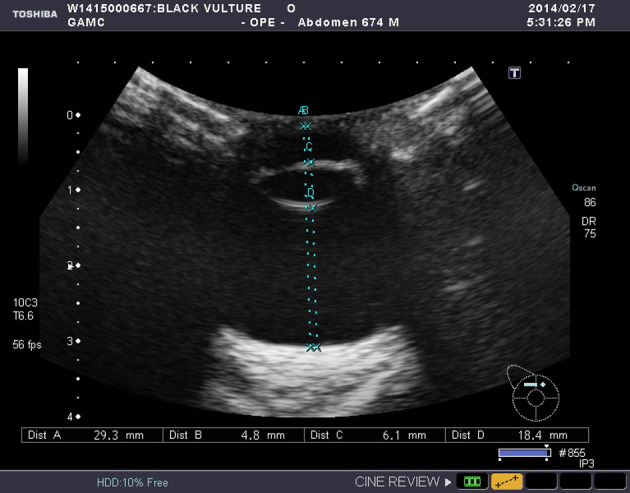

Ultrasonographic examinations and biometry

Ultrasonography was performed with a B-mode ocular unit (Xario, SSA 660A, Toshiba Inc., Japan) with 8 MHz convex transducer. The eyes of raptors were anesthesized by 0.5% proparacaine hydrochloride (Alcaine®, Alcon, Puurs, Belgium) and scanned bilaterally in dorsal plane (oculus dexter (OD), right eye; oculus sinister (OS), left eye). The transducer was positioned directly on the cornea, with ultrasound transmission gel (Fany Sonic®, Taiheung Medical Co., Korea) for contact. Standoff pad was not used (Fig. 1). Additionally, the anterior eye chamber was scanned in the transverse plane with transducer placed at temporal area. With a routine sonography, biometric measurements of the axial length (WL) of lens, length of pecten oculi (LP), depth of the anterior chamber (AC), the axial globe length (LB), and the vitreous chamber (VC) were performed. The images of the transversal scan at 6 hr were used to determine LP. All measurements were taken in dorsal plane at level of lens maximal diameter. During this, ocular surfaces were aligned along with an eye’s central optical axis symmetrically. Measurement were stored on the computer and documented for results.

Fig. 1.

Ultrasonographic examination of the right eye of a cinereous vulture (Aegypius monachus). Standoff pad did not used.